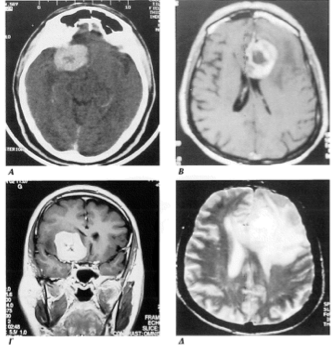

Εικόνα 9α,9β. Μηνιγγίωμα κυρτότητας δεξιού μετωπιαίου λοβού. Διακρίνεται η ευρεία πρόσφυση στη μήνιγγα της κυρτότητας (σε εγκάρσια και στεφανιαία τομή)

Εικόνες 11. Μηνιγγίωμα κυρτότητας αριστερού παρεγκεφαλιδικού ημισφαιρίου. Είναι ιδιαίτερα εμφανής η πίεση και παρεκτόπιση του στελέχους (11Α,Β.Γ,Δ).